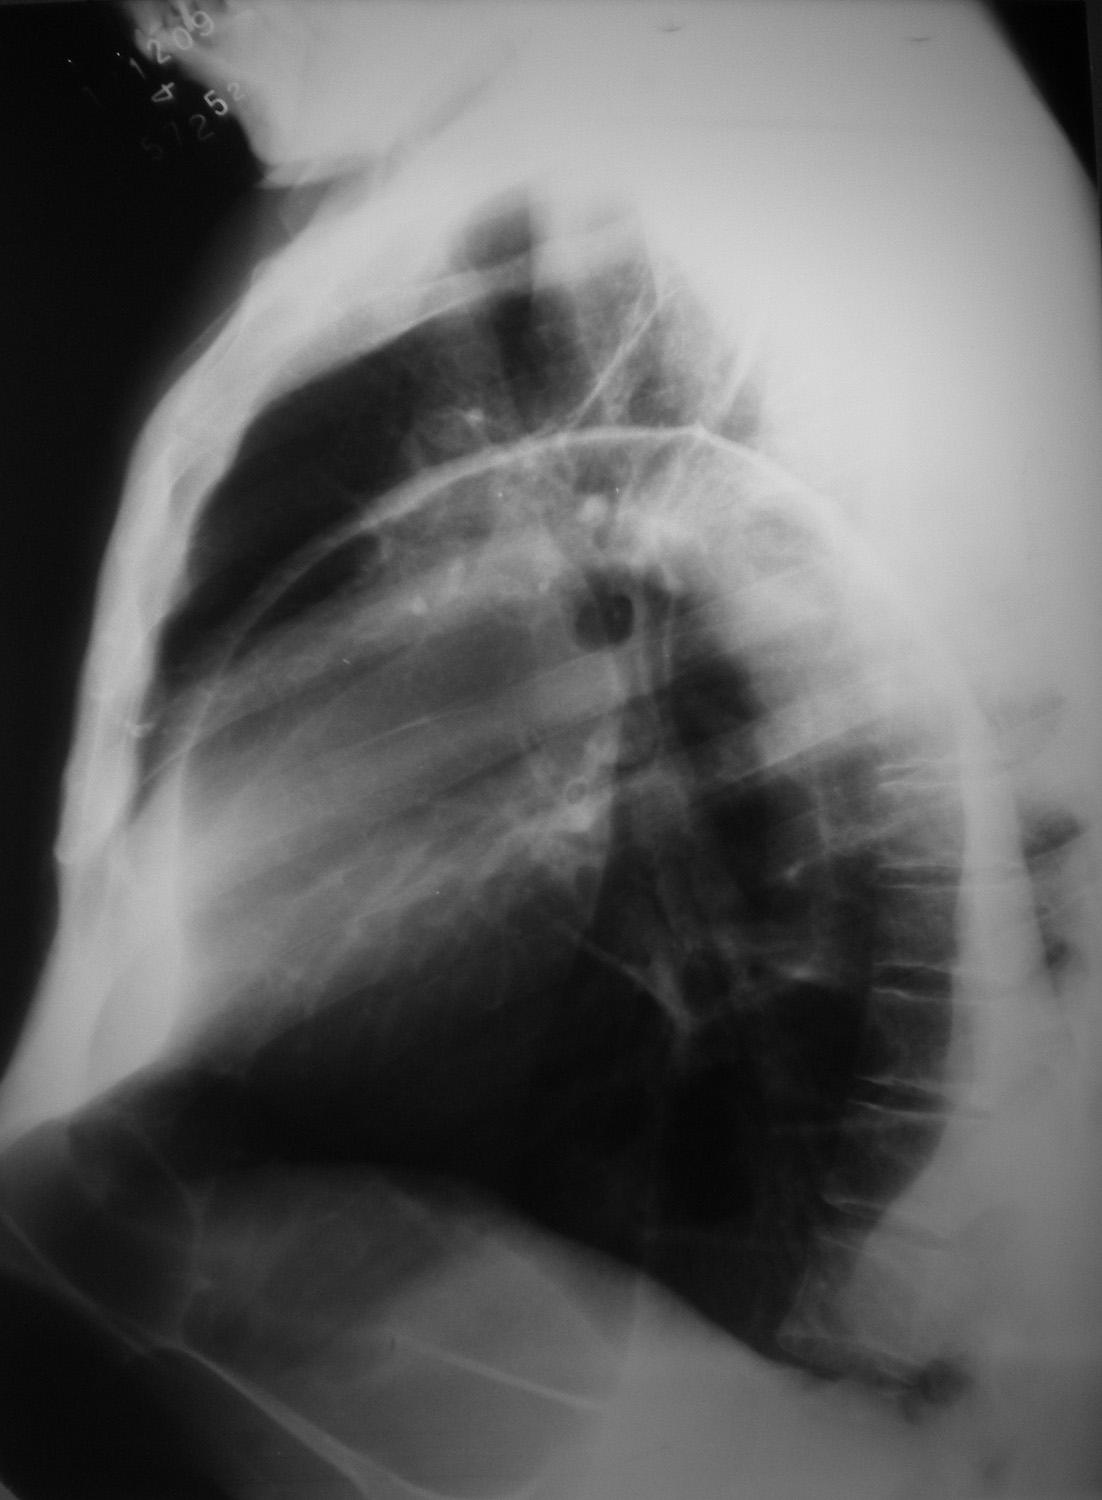

Eventração diafragmática

Diaphragmatic Eventration

Caso Código 129A de Eventração diafragmática - Case Code 129A of Diaphragmatic Eventration

Rx de tórax, em perfil, evidenciando grande eventração do diafragma.